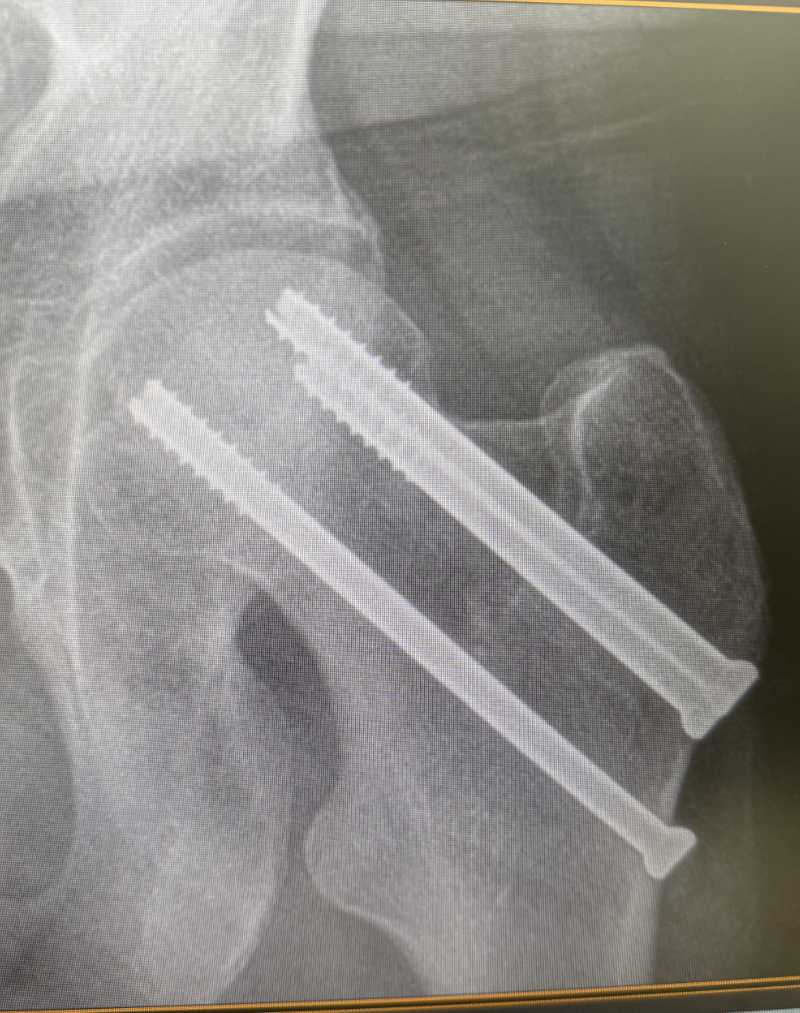

xray fixed injury Orthoedge

Hip fractures (femoral neck, intertrochanteric)

Hip fracture with 3 screws.